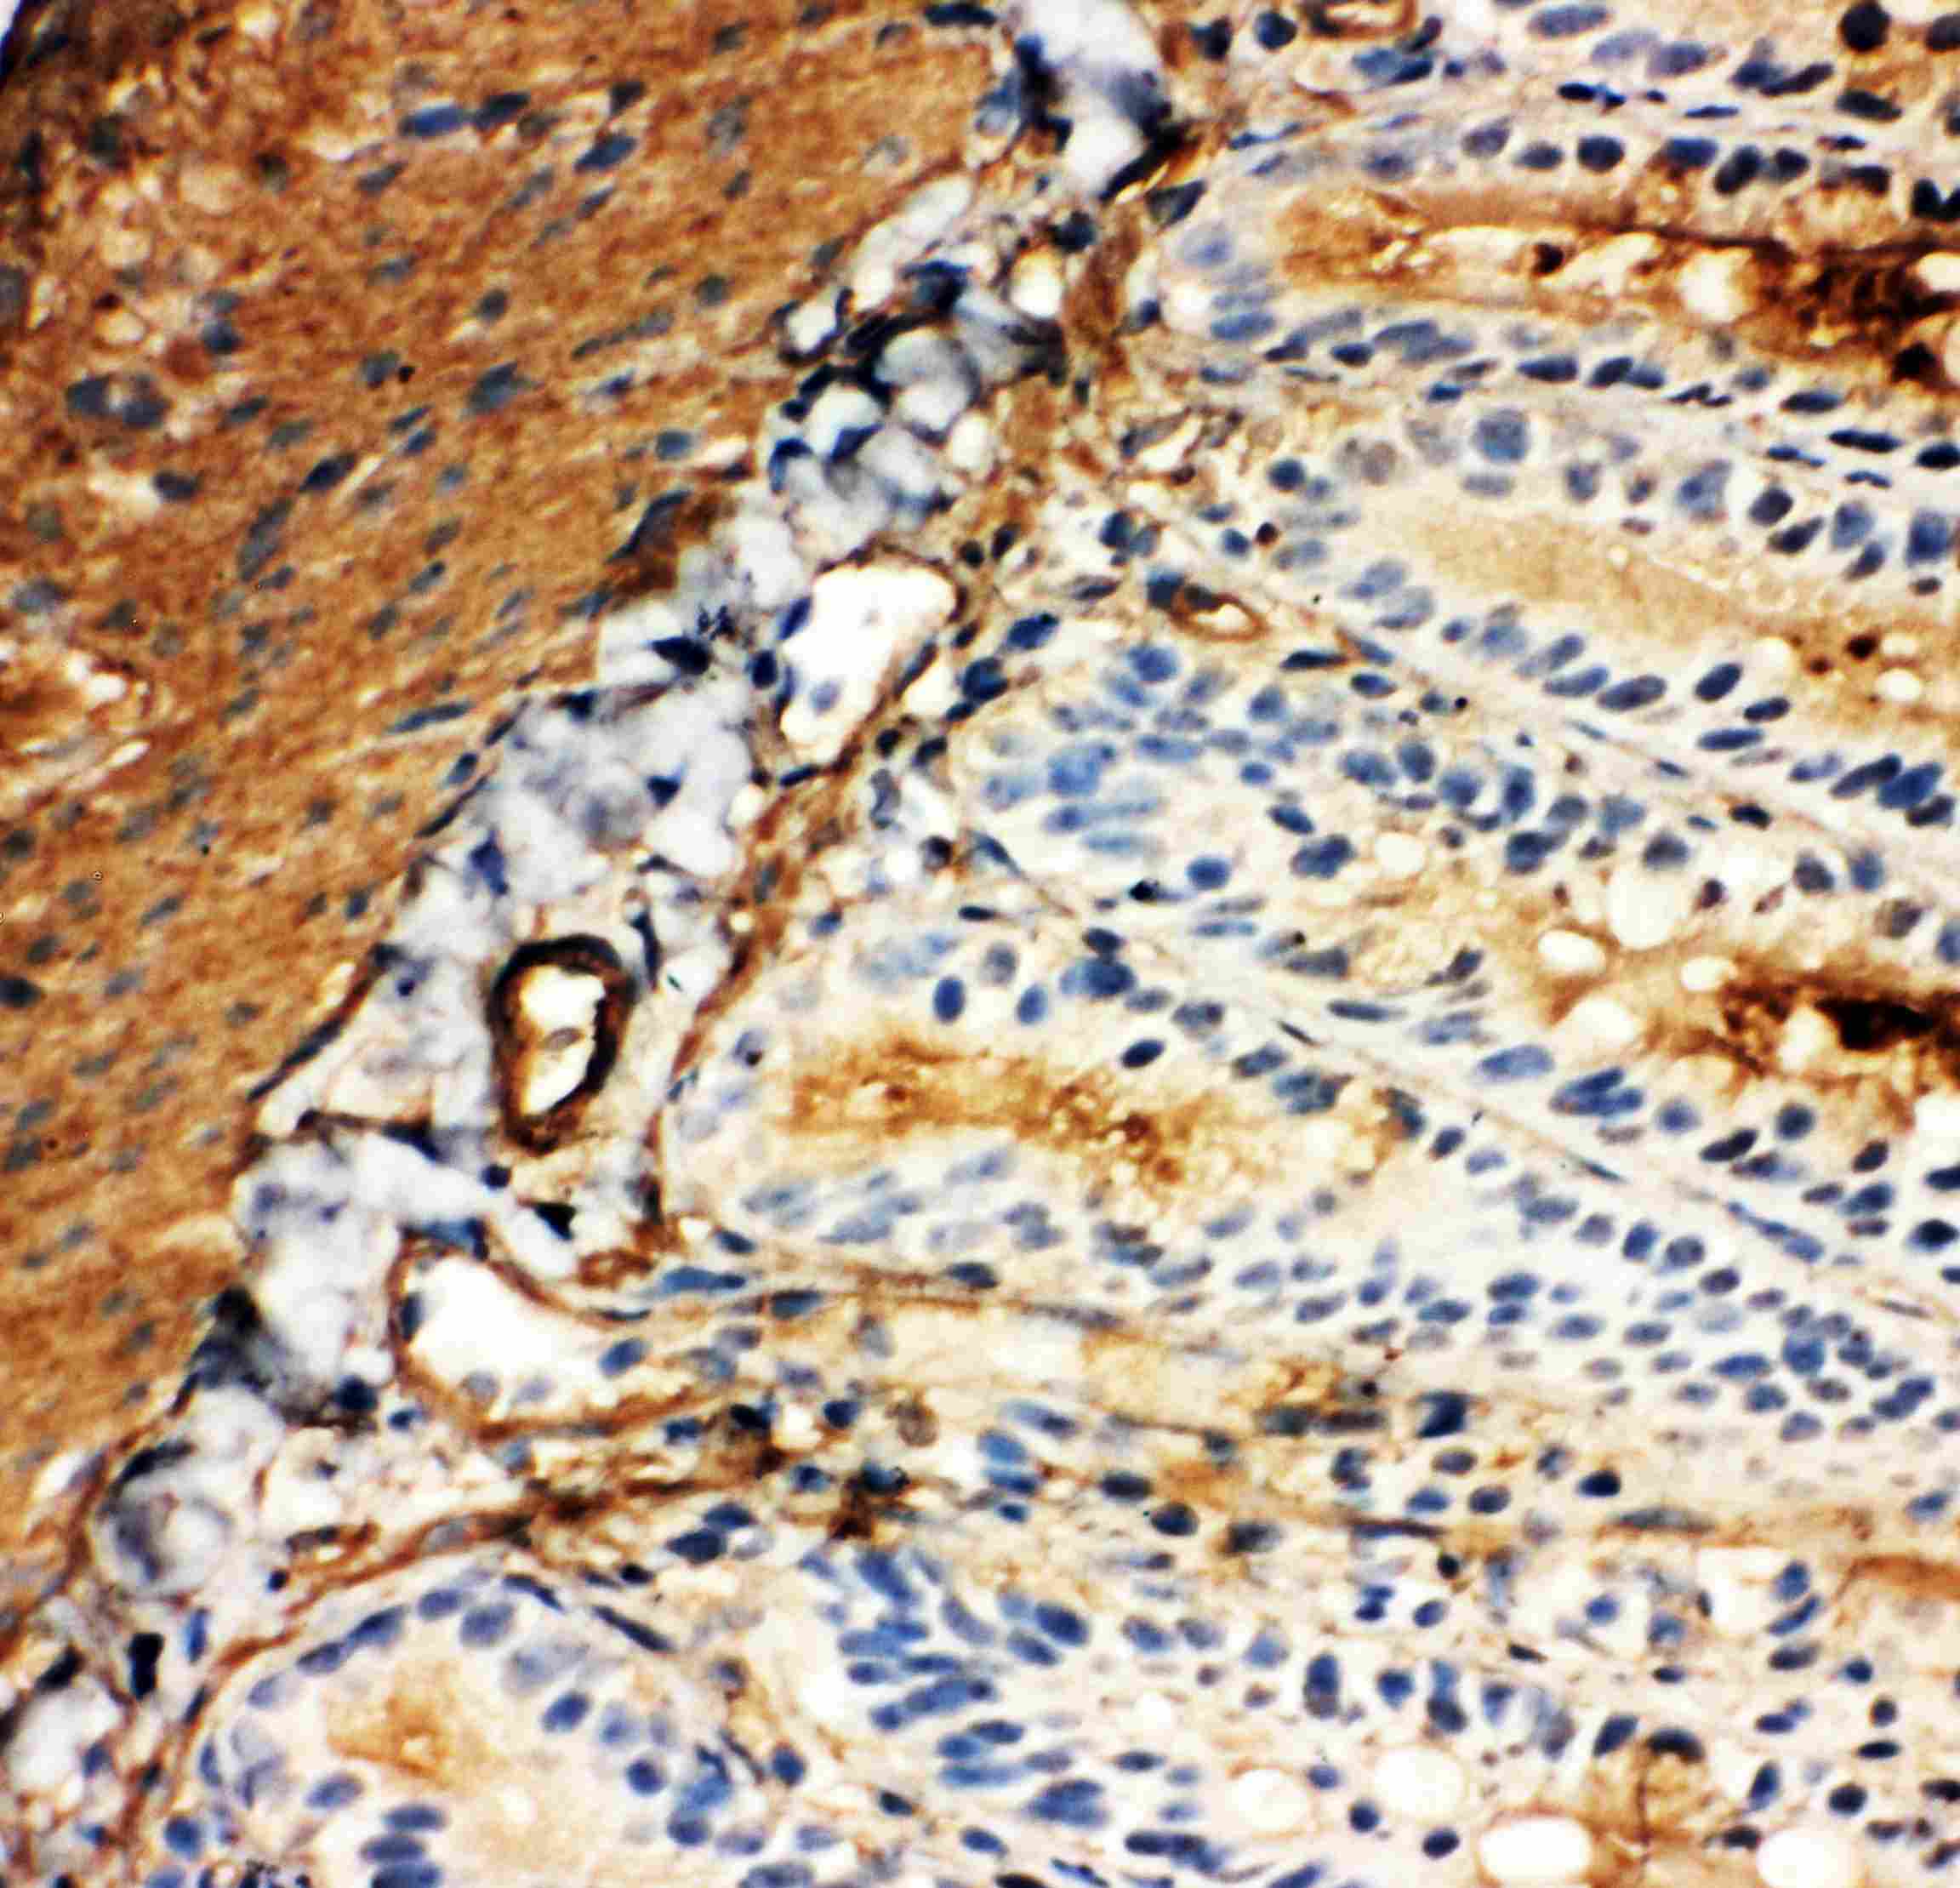

IHC-P analysis of rat kidney tissue using GTX12098 GLUT5 antibody.

IHC-P analysis of mouse tissue using GTX12098 GLUT5 antibody.

Antigen retireval : Heat mediated antigen retrieval was performed in citrate buffer (pH6, epitope retrieval solution) for 20 mins

Dilution : 1μg/ml